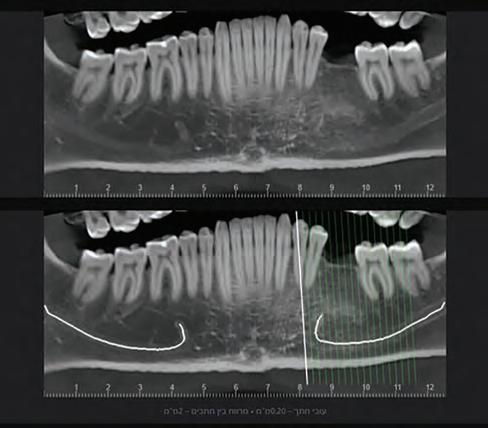

I have been using artificial intelligence tools throughout the examination of all my patients since 2019. I will now present a number of clinical cases from my daily practice, in which artificial intelligence was used as an aid for making informed decisions in diagnosis and treatment planning. It must be said that I deliberately chose routine cases and not “heroic battle tales”. In my presentation below, I will focus on the process

Fig. 1a: A panoramic reformatting of the CBCT scan, made by artificial intelligence, with automatic marking of the inferior alveolar nerve canal.)

Fig. 1b: A panoramic reformatting of the CBCT scan, performed by a human radiographer, with manual marking of the inferior alveolar nerve canal.)

Fig 2: Automatic measurement of the height and width of the alveolar ridge at the designated implantation site (Diagnocat, Diagnocat Inc., USA).

R., a 40-year-old male, came to the dental clinic due to a previously extracted tooth #19 (ISO 36), and asked for an implant-supported crown to be placed. He was referred for a CBCT at an imaging center, and the resulting 3D volume was uploaded to an artificial intelligence system (Diagnocat, Diagnocat Inc., USA) to perform automatic slicing, detection of the inferior alveolar nerve, and alveolar ridge measurements. Parallel to that, a human radiographer in the imaging center created a manual cross-sections report, that was attached to the 3D DI-COM file.

In the panoramic reformatted image produced as part of the AI-based cross-sections report, it seemed that the pathway of the inferior alveolar nerve forms a loop towards the mandibular foramen, close to the future transplant site. (Fig. 1A) It is unfortunate to mention that a human interpreter

did not mark this loop, (Fig 1B) perhaps due to alternate positioning of the panoramic cross-section.

In light of this discrepancy, I ordered a rendering of the 3D volume to a digital STL model, in order to further appraise the distance between the mandibular foramen and the planned implant placement site. The cross-sectional measurements (Fig. 2) and the segmentation to a 3D model (Fig. 3) were carried out by the same artificial intelligence system (Diagnocat, Diagnocat Inc., USA). These made it possible to understand the exact location of the nerve, and to make sure that it was indeed out of range of danger in this case.